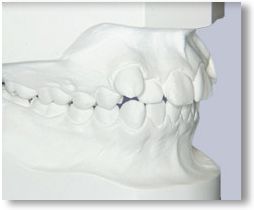

RECORDS